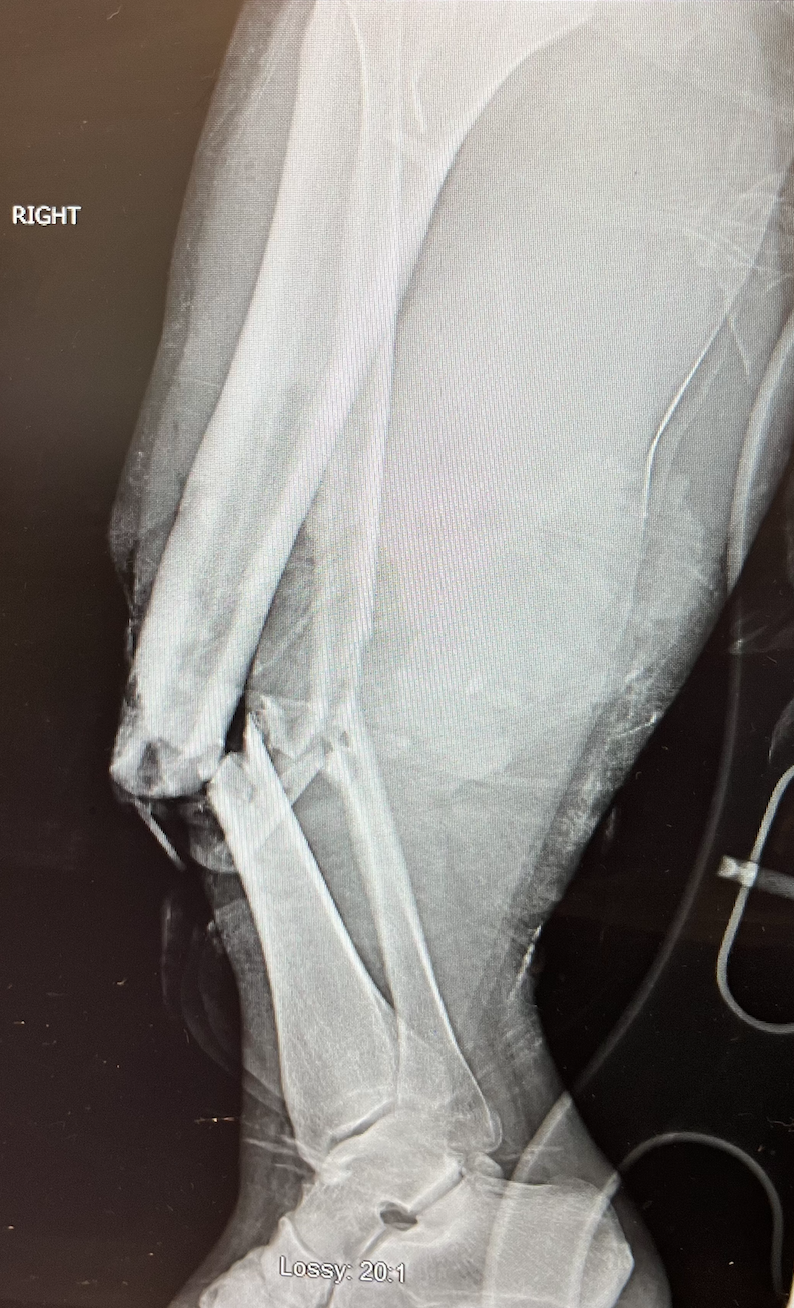

Fracture Care

Fractures of the foot and ankle can range from subtle stress fractures caused by overuse to more severe, traumatic breaks that require immediate attention. Because the foot and ankle bear the weight of your body, proper alignment and healing are critical to preventing long-term complications like chronic pain or early-onset arthritis. Care often begins with advanced imaging to determine the exact nature of the break. Depending on the severity, treatment may involve non-surgical stabilization using specialized walking boots, casts, or splints to allow the bone to heal on its own. In other cases where the fracture is unstable, surgical intervention may be necessary to restore proper alignment. From the initial injury through rehabilitation and a safe return to activity, a podiatrist ensures you get proper treatment to heal optimally so you are ready for the road ahead.